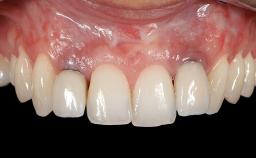

Soft-Tissue Augmentation Using a Porcine-Derived Collagen Matrix to Correct a Labial Soft-Tissue Defect Following Extraction of a Maxillary Incisor

In this case, Shakeel Shahdad employs a two-layer matrix to repair a soft-tissue defect in a post-extraction healed site prior to implant placement with simultaneous guided bone regeneration. This approach resulted in a gain of keratinized peri-implant mucosa with optimal shade and texture. Soft-tissue defects are often encountered prior to implant placement and may result in deficient attached keratinized mucosa, which unless corrected will yield less than ideal esthetic outcomes. The presence of keratinized mucosa has been proposed as one of the prognostic factors for the survival of dental implants (Adell and coworkers 1986) with reported greater reductions in gingival and plaque indices after increasing the width of keratinized mucosa by soft-tissue augmentation (Giannobile and coworkers 2018; Thoma and coworkers 2018).